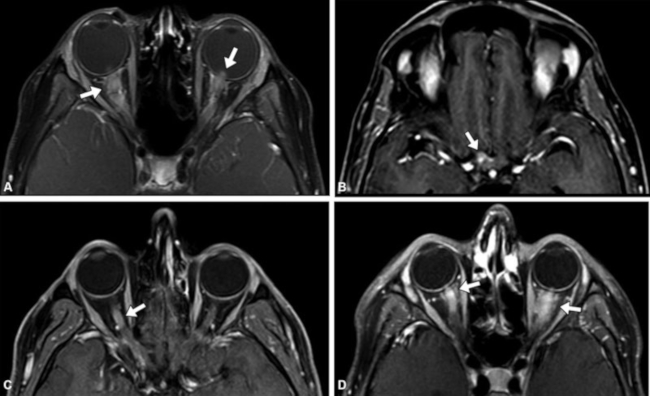

En el diagnóstico diferencial de la neuroretinitis por B. Henseleae se debe tener en cuenta principalmente la neuritis óptica de etiología desmielinizante como la producida en contexto de esclerosis múltiple (EM), neuromielitis óptica (NMO), anticuerpos contra la glicoproteína de mielina-oligodendrocitos (anti-MOG) y encefalomielitis aguda diseminada (ADEM), entidades que por lo general presentan cambios inflamatorios de mayor extensión y en segmentos posteriores del nervio óptico.10,11 Además, esas patologías, en caso de presentar compromiso del segmento intraocular, generalmente se asocian a realce de segmentos posteriores (Fig. 2) a diferencia del realce focal característico de la neuroretinitis por B. Henseleae. También se deben tener en cuenta otras causas de neuroretinis que igualmente deben considerarse en el diagnóstico diferencial, entre ellas enfermedades infecciosas o inflamatorias como la toxoplasmosis, toxocariasis, tuberculosis, sífilis, enfermedad de Lyme, rickettsiosis, sarcoidosis, enfermedad de Behçet.12 Por otro lado, debemos considerar que existen condiciones clínicas que pueden confundirse con el diagnóstico de neuroretinitis por causar edema de papila y estrella macular. Entre ellas se encuentran la hipertensión arterial, la diabetes mellitus, la hipertensión endocraneana, la oclusión de rama venosa de la retina y la neuropatía óptica isquémica anterior.13